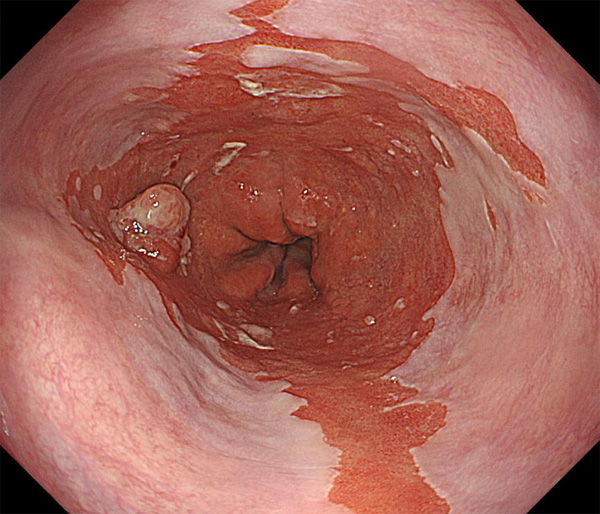

2026年1月24日開催の第19回研究会でご提示した検討症例です。 (画像をクリックすると拡大します)

2025年7月19日開催の第18回研究会でご提示した検討症例です。 (画像をクリックすると拡大します)

2025年1月11日開催の第17回研究会でご提示した検討症例です。 (画像をクリックすると拡大します)

2024年6月29日開催の第16回研究会でご提示した検討症例です。 (画像をクリックすると拡大します)

2024年1月6日開催の第15回研究会でご提示した検討症例です。 (画像をクリックすると拡大します)

2023年7月1日開催の第14回研究会でご提示した検討症例です。 (画像をクリックすると拡大します)

2023年1月21日開催の第13回研究会でご提示した検討症例です。 (画像をクリックすると拡大します)

2022年7月2日開催の第12回研究会でご提示した検討症例です。 (画像をクリックすると拡大します)

2022年1月22日開催の第11回研究会でご提示した検討症例です。 (画像をクリックすると拡大します)

2021年6月26日開催の第10回研究会でご提示した検討症例です。 (画像をクリックすると拡大します)

2021年1月23日開催の第9回研究会でご提示した検討症例です。 (画像をクリックすると拡大します)

2020年1月25日開催の第8回研究会でご提示した検討症例です。 (画像をクリックすると拡大します)

2019年1月12日開催の第6回研究会でご提示した検討症例です。 (画像をクリックすると拡大します)

2018年6月30日開催の第5回研究会でご提示した検討症例です。 (画像をクリックすると拡大します)

2017年7月15日開催の第3回研究会でご提示した検討症例です。 (画像をクリックすると拡大します)

2017年1月7日開催の第2回研究会でご提示した検討症例です。 (画像をクリックすると拡大します)

2016年6月4日開催の第1回研究会でご提示した検討症例です。 (画像をクリックすると拡大します)